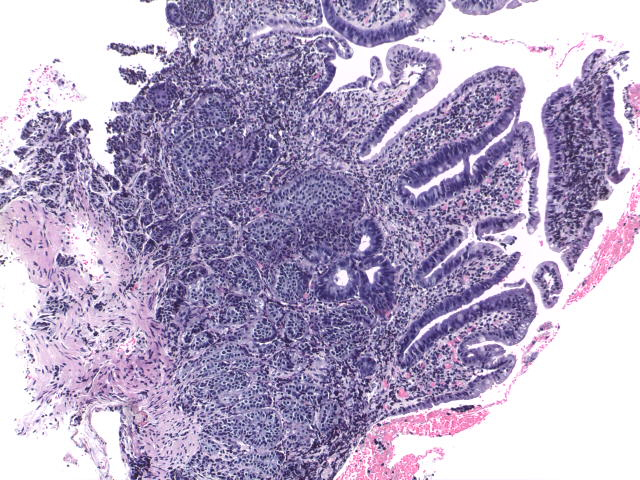

Hombre de 55 años con padecimiento de 1 año de evolución caracterizado por melena, astenia, adinamia y anemia. En enteroscopía se observaron múltiples lesiones subepiteliales en intestino delgado de una de las cuales se tomó biopsia.

Se realizó cirugía en la que se identificaron múltiples nódulos en ileon , entre los 80 y 120 cm de la válvula ileocecal. Se procedió a resección segmentaria de intestino.

Biopsia:

Tumor neuroendocrino bien diferenciado grado 1